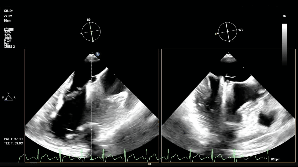

调整瓣膜夹位置

再次捕获瓣叶

第二次关闭瓣膜夹

测量前后瓣距离

释放夹子

术后平均压差为4mmHg